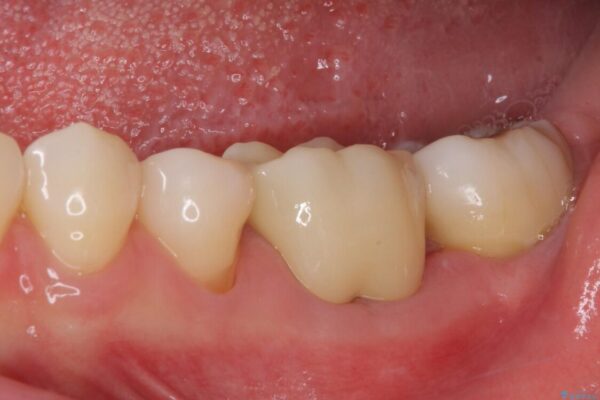

治療後

• むし歯で歯茎から血が出てくる オールセラミッククラウンでの補綴治療 治療後画像

術後6ヶ月でレントゲン写真を撮影したところ、出血の原因であった穴付近の溶けていた骨が回復している様子が認められました。